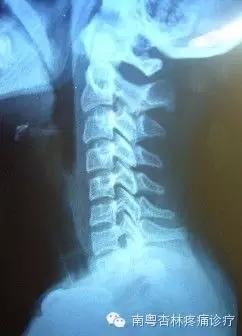

通过X线片上的颈椎显像:沿此曲度走行,在各个颈椎椎体后缘都有形成的连续、光滑的弧形曲线,医学上称之为颈椎曲度。当长时间不正确的坐姿、或是长时间的劳累、颈椎缺少活动、脊柱损伤、脊柱钙化等就会导致颈椎生理曲度变直。

生理曲度变直